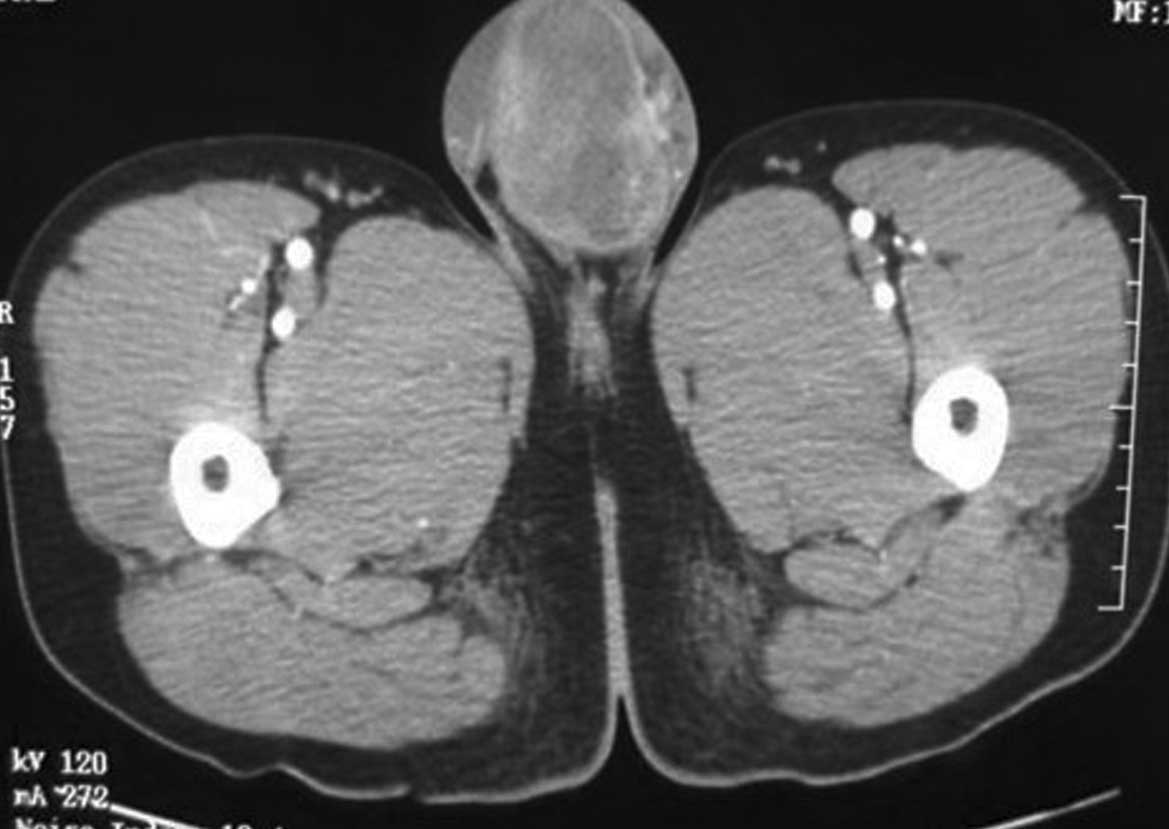

Primary desmoplastic small round cell tumor of the testis: A case report and review of the literature

Desmoplastic small round cell tumors (DSRCTs) are extremely rare and mainly affect adolescents and young adults. The tumors are usually involved with the abdominal area and/or the pelvic peritoneum. Only a small number of cases have been reported concerning DSRCTs of the testicular region. The present study reports a case of DSRCT of the testis with radical orchectomy and systemic chemotherapy, leaving the patient disease-free for 14 months. However, the patient died of multiple metastasis 12 months later. Furthermore there is a review of the English literature to analyze the incidence, site of origin, imaging and pathological characteristics of DSRCT.

Figure 2